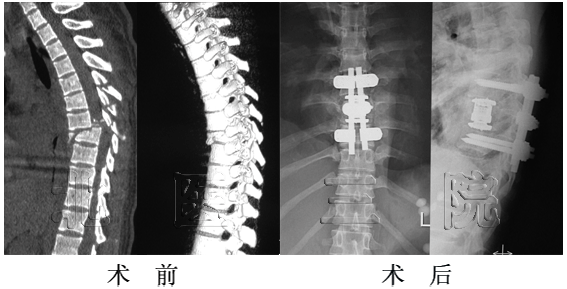

某男,57岁,强直型脊柱炎胸腰段后凸畸形,双下肢无力伴大小便功能障碍.单纯后路前方张开后方闭合截骨矫形术

男,L1陈旧骨折后凸畸形,下肢不全瘫,,单纯后路经椎间隙闭合截骨矫形